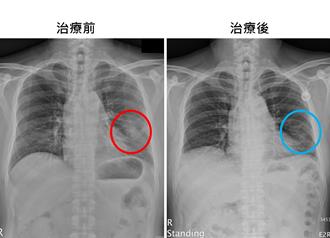

肺癌長期蟬聯國人癌症死因榜首,其中約70%為肺腺癌病人。過去因健保給付限制,約30%無基因突變的第4期肺腺癌病人,只能選擇傳統化學治療或自費接受免疫治療,治療方式相對受限。健保署從今年6月1日起,將免疫治療合併化學治療納入健保給付範圍,苗栗縣大千綜合醫院醫療副院長暨胸腔內科醫師謝為忠表示,這項政策不僅與國際治療指引完全接軌,更為病人帶來治療新希望。